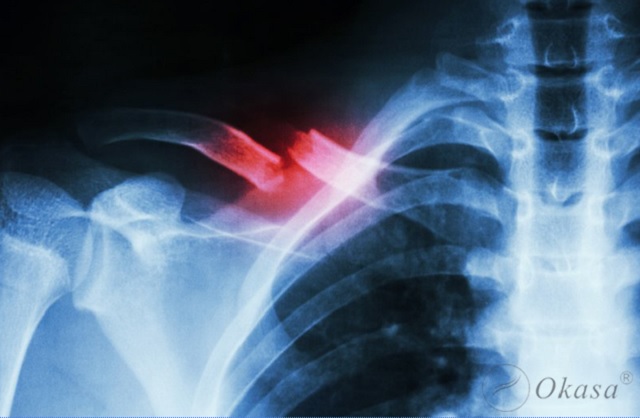

Xương quai xanh có nhiệm vụ vô cùng quan trọng, đó là nơi nối để xương cánh tay được treo vào thân. Khi bị chấn thương vùng vai dễ dẫn tới gãy xương quai xanh. Thông thường người bị gãy hoặc lệch xương quai xanh là do bị ngã hoặc bị tai nạn giao thông.

Cấu trúc mạch máu thần kinh chạy phía dưới xương đòn, điểm chuyển tiếp thay đổi thiết diện ngang nằm tại chỗ nối 1/3 giữa và 1/3 ngoài của xương đòn, đây chính là vị trí yếu nhất của xương cũng là nơi dễ gãy nhất.

- Ngoài ra, bác sĩ sẽ chỉ định chụp X-quangcho người bệnh ở bình diện thẳng và tư thế đặc biệt của xương quai xanh để đánh giá sự xê dịch trước sau của 2 đoạn gãy.